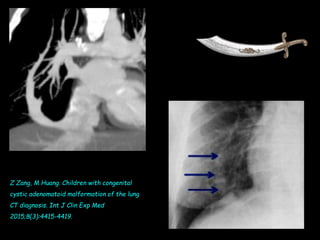

• Recherche de malformations associées :

– Syndrome du cimeterre : retour pulmonaire

veineux anormal droit vers la veine cave

inférieure

– Malformation adénomatoïde

– Dextrocardie

– Anomalie de retour veineux

Z Zang, M Huang. Children with congenital cystic adenomatoid malformation of the lung CT

diagnosis. Int J Clin Exp Med 2015;8(3):4415-4419.

Z Zang, M Huang. Children with congenital

cystic adenomatoid malformation of the lung

CT diagnosis. Int J Clin Exp Med

2015;8(3):4415-4419.